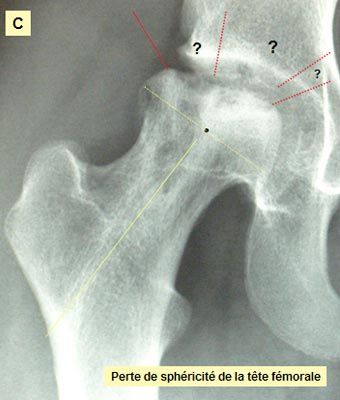

Que se passe t'il à l'intérieur de l'os ? Clichés comparatifs intermédiaires - A : L'IRMN avant la greffe de biomatériau montre l'étendue de la nécrose sur la hanche de face. - B : L'IRMN postopératoire à 10 mois précise l'étendue de la nécrose dans la tête fémorale « in situ ». - C : Les Rx standards pré et postopératoire à 16 mois précisent l'évolution de la nécrose. - D : Les Rx standards post - opératoire à J + 1 et à 16 mois précisent l'évolution du biomatériau. ETENDUE de la NÉCROSE

EVOLUTION de la NÉCROSE

Sur le plan radiographique : - La zone nécrotique est nettoyée. - L'aplatissement de la tête fémorale ne s'est pas aggravé depuis l'intervention. - le corail naturel est résorbé au niveau du col ; il est partiellement résorbé au niveau de la tête fémorale.